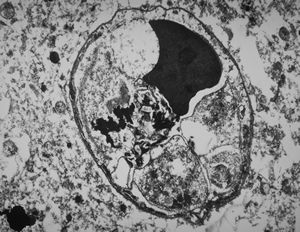

rabbit spinal cord trauma